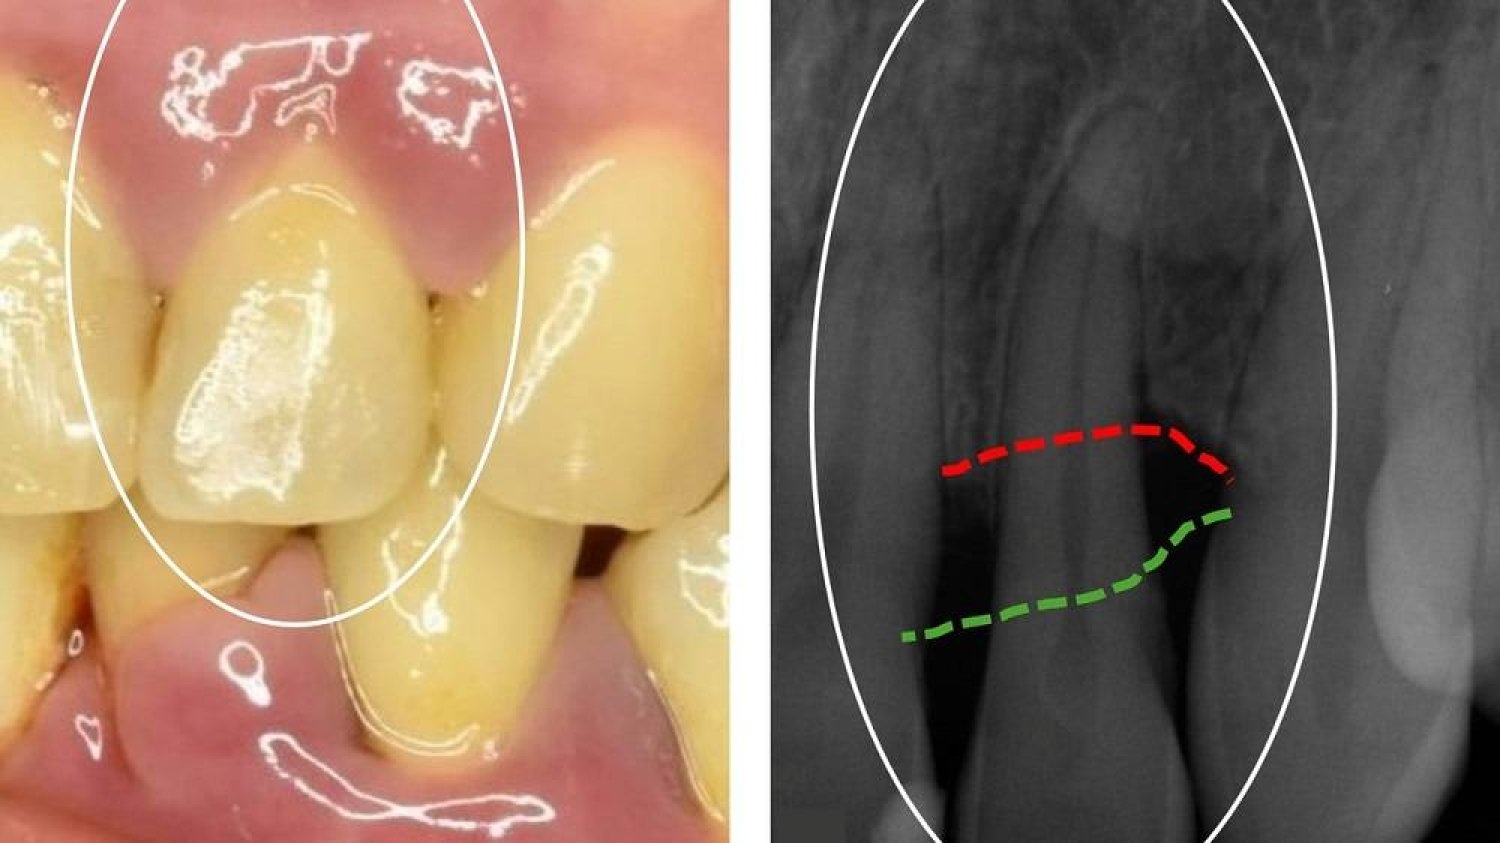

والتهاب اللثة هو مرض مزمن يصيبها، ويُسبّب تهيّجاً وإحمراراً وتورُّماً ونزيفاً في أجزائها المحيطة بقاعدة الأسنان، نتيجة تراكم «البلاك»؛ وهو طبقة لزجة تتكوّن أساساً من البكتيريا.

ومع الوقت، يمكن أن تتصلّب الطبقات اللزجة، وتتحوّل إلى «جير»، وتسبّب تهيُّج أنسجة اللثة والتهابها، ومن ثمّ تنتج فجوات عميقة بين الأسنان واللثة، حيث تزدهر البكتيريا.

ويؤدّي التهاب اللثة إلى تآكل الأنسجة الداعمة للأسنان، وفي الحالات الحادة يمكن أن يؤدّي إلى فقدانها.